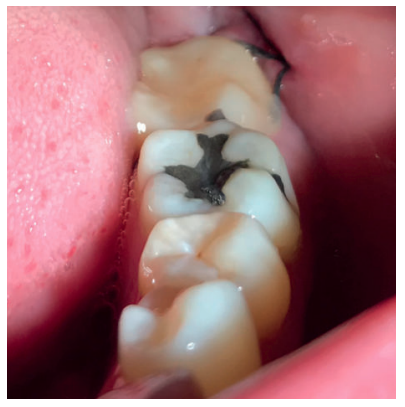

Tras obtener el consentimiento informado, se realizó un bloqueo anestésico mediante Articaína al 4% con adrenalina 1:100.000 del nervio dentario inferior y lingual, y posteriormente el nervio bucal. Se realizó una incisión festoneada lineal desde la cara distal del primer molar inferior izquierdo, hasta la cara distal del segundo molar inferior izquierdo, y se realizó una incisión oblicua hacia la rama ascendente mandibular. Tras el despegamiento mucoperióstico, se realizó una protección del nervio lingual durante las maniobras de ostectomía. Posteriormente se realizó la ostectomía necesaria para liberar el límite amelocementario del tercer molar inferior, procediendo a su luxación mediante botador recto, odontosección coronal con pieza de mano y fresa redonda de carburo de tungsteno, y exodoncia del fragmento radicular una vez retirado el fragmento coronal (Figura 2). El alveolo se lavó con suero fisiológico y se le hizo al paciente morder una gasa estéril empapada en clorhexidina al 0,12%, durante la preparación del material de injerto.

Los fragmentos coronal y radicular se limpiaron de restos de tejidos blandos, y secos, se introdujeron en la máquina Smart Dentin Grinder® (Kometa Bio, BIONER, España). Tras un ciclo de triturado de 3 segundos, y otro de tamizado de 20 segundos, el material obtenido (Figura 3) se limpió con la primera solución durante 12 minutos, y después durante 3 minutos con la segunda solución, para después transportar el material de injerto al alveolo, con presión controlada (Figura 4). Una vez compactado, se colocó una esponja de fibrina (Gelatamp® ) (Figura 5) y se suturó la herida con seda de 4/0, mediante dos puntos simples en la cara distal del segundo molar inferior izquierdo, un punto en cruz en la descarga y un punto en la papila (Figura 6). Se realizó una radiografía periapical intraoperatoria (Figura 7).